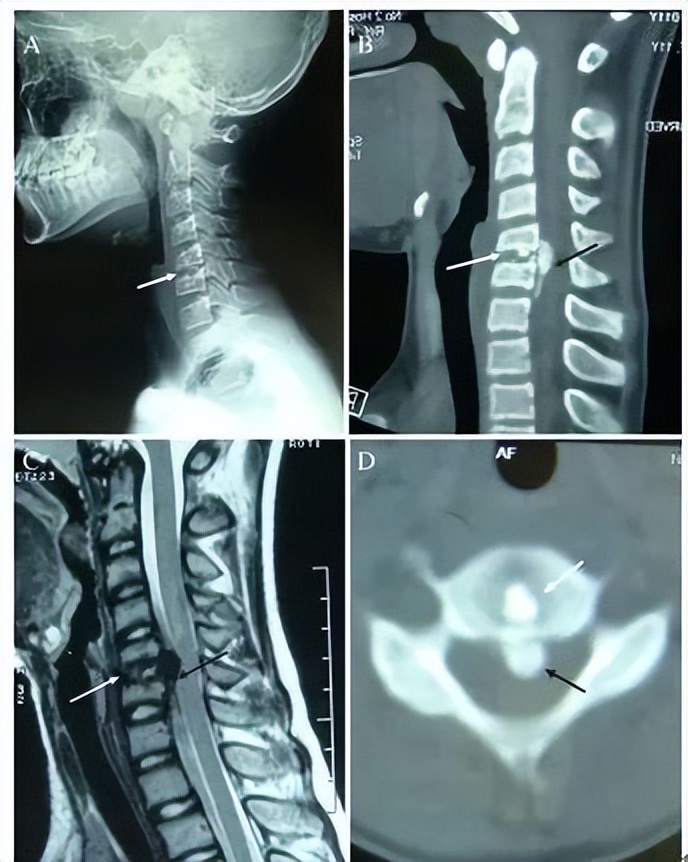

图:患者8岁,女孩,因严重颈部疼痛、活动受限伴左上肢无力、麻木不适2天就诊。既往有锁骨骨折、额部软组织挫伤病史。查体:颈椎活动受限,左上肢肌力正常,但感觉减退。白细胞、血沉、CRP升高。颈椎侧位片和CT平扫提示C6-7椎间盘钙化(粗箭头)和后纵韧带骨化(细箭头),颈椎MRI提示C6-7水平脊髓明显受压。给予颈椎制动、枕颌带2.5kg颈椎牵引2周。随后,颈托固定1个月。2年后随访复查颈椎CT如下图,同时上述症状完全缓解。

图:2年后复查CT示C6-7钙化的椎间盘和后纵韧带骨化都消失了